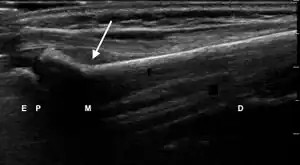

| 1 | Angulation of the distal bone segment[14] | ![]() Ultrasound view of angulation of distal bone segment (shown by arrow). E = epiphysis; P = physis; M = metaphysis; D = diaphysis. | |